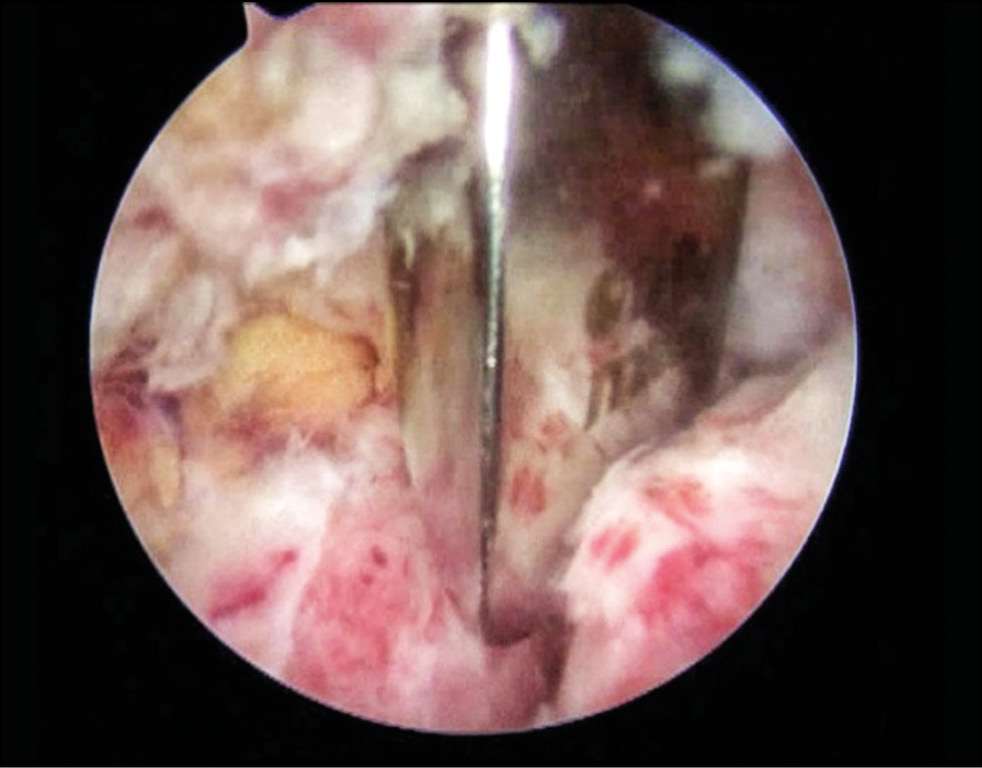

At the Stage 3, under arthroscopic control of the musculocutaneous nerve, a split was formed in the tendon of the subscapularis muscle strictly parallel to the course of the fibers at the border of the middle and lower thirds using a coblator. Next, the Wilmington port was installed and the wires were passed using a double-barrel guide marked α and β, strictly parallel to the vertical axis along the midline of the coracoid process (Fig. 9).

Fig. 9. Conducting the wires in the coracoid process: a — installation of the guide pin; b — conduction of the guidewires.